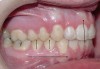

If the maxillary anterior teeth are positioned or inclined palatally, upon closure the lower teeth are going to first contact these teeth, which will force the mandible to shift to close into a retruded position. The objective is to try to identify this shift from primary contact to closure. This type of fence could potentially lead to shifting of the maxillary anterior teeth, breaking of the teeth, and/or muscular and jaw dysfunction as a result of posterior displacement of the mandible (Figures 2 through 5).

Figure 2

Figure 3

Figure 4

Figure 5